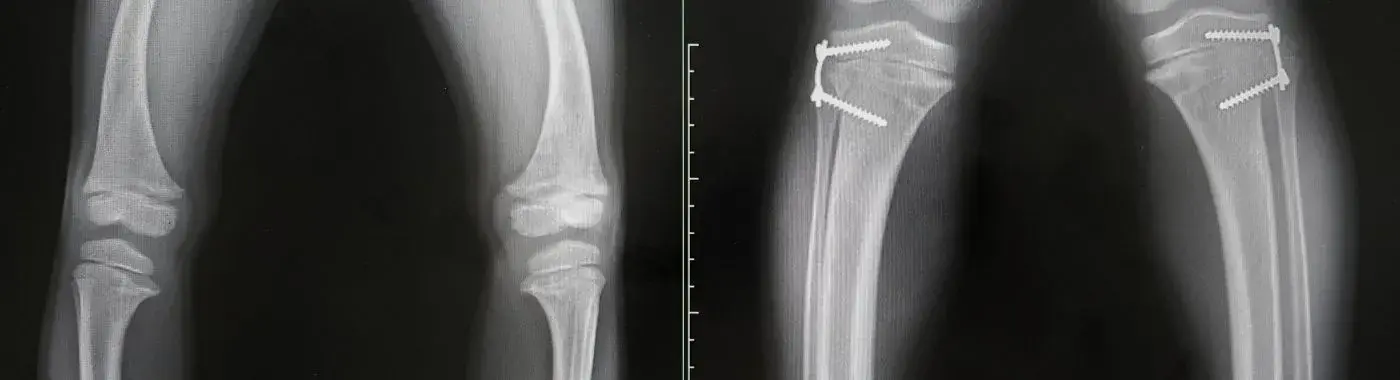

2. X-rays:

• X-rays of the bones can help detect fractures, bone deformities, and signs of reduced bone density associated with osteomalacia. However, X-rays may not show early changes in bone mineralization.